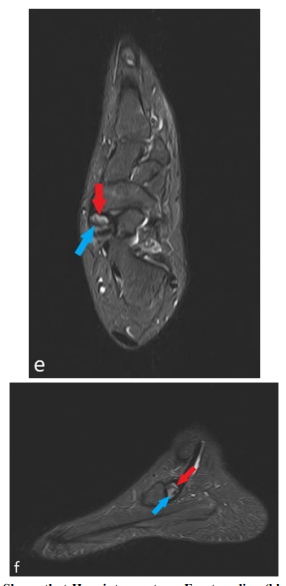

Axial STIR (e) and Sagittal STIR (f) Shows that Hypointense stress Fracture line (blue arrow) and Hyperintense Avascular Necrosis (red arrow)